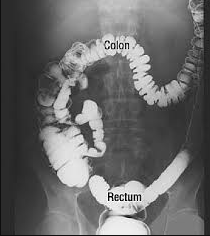

The colon is made up of the large intestine. It extends from the end of the ileum to the anal canal that surrounds the anus. An ulcer is defined as an open sore or lesion of the skin or mucous membrane. Ulcerative colitis is a chronic, nonspecific, inflammatory and ulcerative illness in the colonic mucosa. The condition is characterized most often by bloody diarrhea.

History and stool examinations usually provide reasonable evidence for the diagnosis. This diagnosis needs further confirmation. A total colonoscopy is normally necessary before treatment begins. Using an instrument to view the area, or having a barium enema during active episodes of the condition, might cause further trauma (e.g., perforation, hemorrhage and inflammation). However, these procedures are usually indicated later in the course of the disorder to determine the extent of colon involvement.